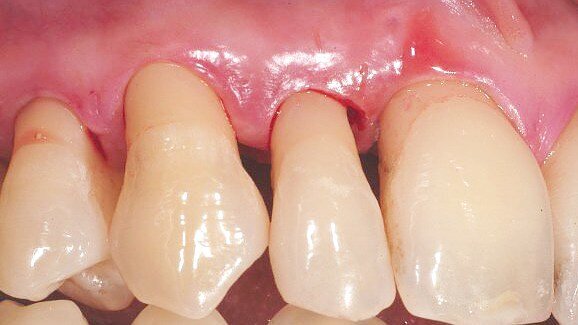

Burkhardt & Lang in 2005 clearly showed that a microsurgical technique led to better healing than the classical technique.(1) The key to the success of microsurge is maintaining the integrity of the tissues and in particular their vascularisation—so much so that a surgical technique can be qualified as minimally invasive when it safeguards tissue vascularisation.

In this type of surgery, attention must be paid to the thinness of the anatomic structures, namely of the different tissue planes being operated on. Just as plastic surgeons treat skin tissues plane by plane, the periodontist should handle the periodontium in the same way, taking account of the anatomic and functional specificity of each plane. The thinness of the structures to be operated on calls for a microsurgical approach.

With plane-by-plane surgery it is possible to respect the various anatomic structures, as well as to manage possible tissue tensions that could be harmful to the revascularisation of the surgery site, as brilliantly demonstrated in Mammoto’s article published in the well-known Nature review in 2009.(2) The develop ent of endothelial cells, seat of the vascularisation process, is influenced by tension receivers which guide the tissue morphology in particular during tissue healing.

Avoiding periosteum detachment

The periosteum is a fundamental vascular source for the periodontium. Full thickness flaps, or even partial thickness flaps, induce a delay in healing and bone resorptions, as noted in the recent study by Fickl et al.(5) Flapless surgery or surgery using partial thickness techniques considerably improves the healing process: this has long been studied (6-8) and is made possible precisely by microsurgical techniques.